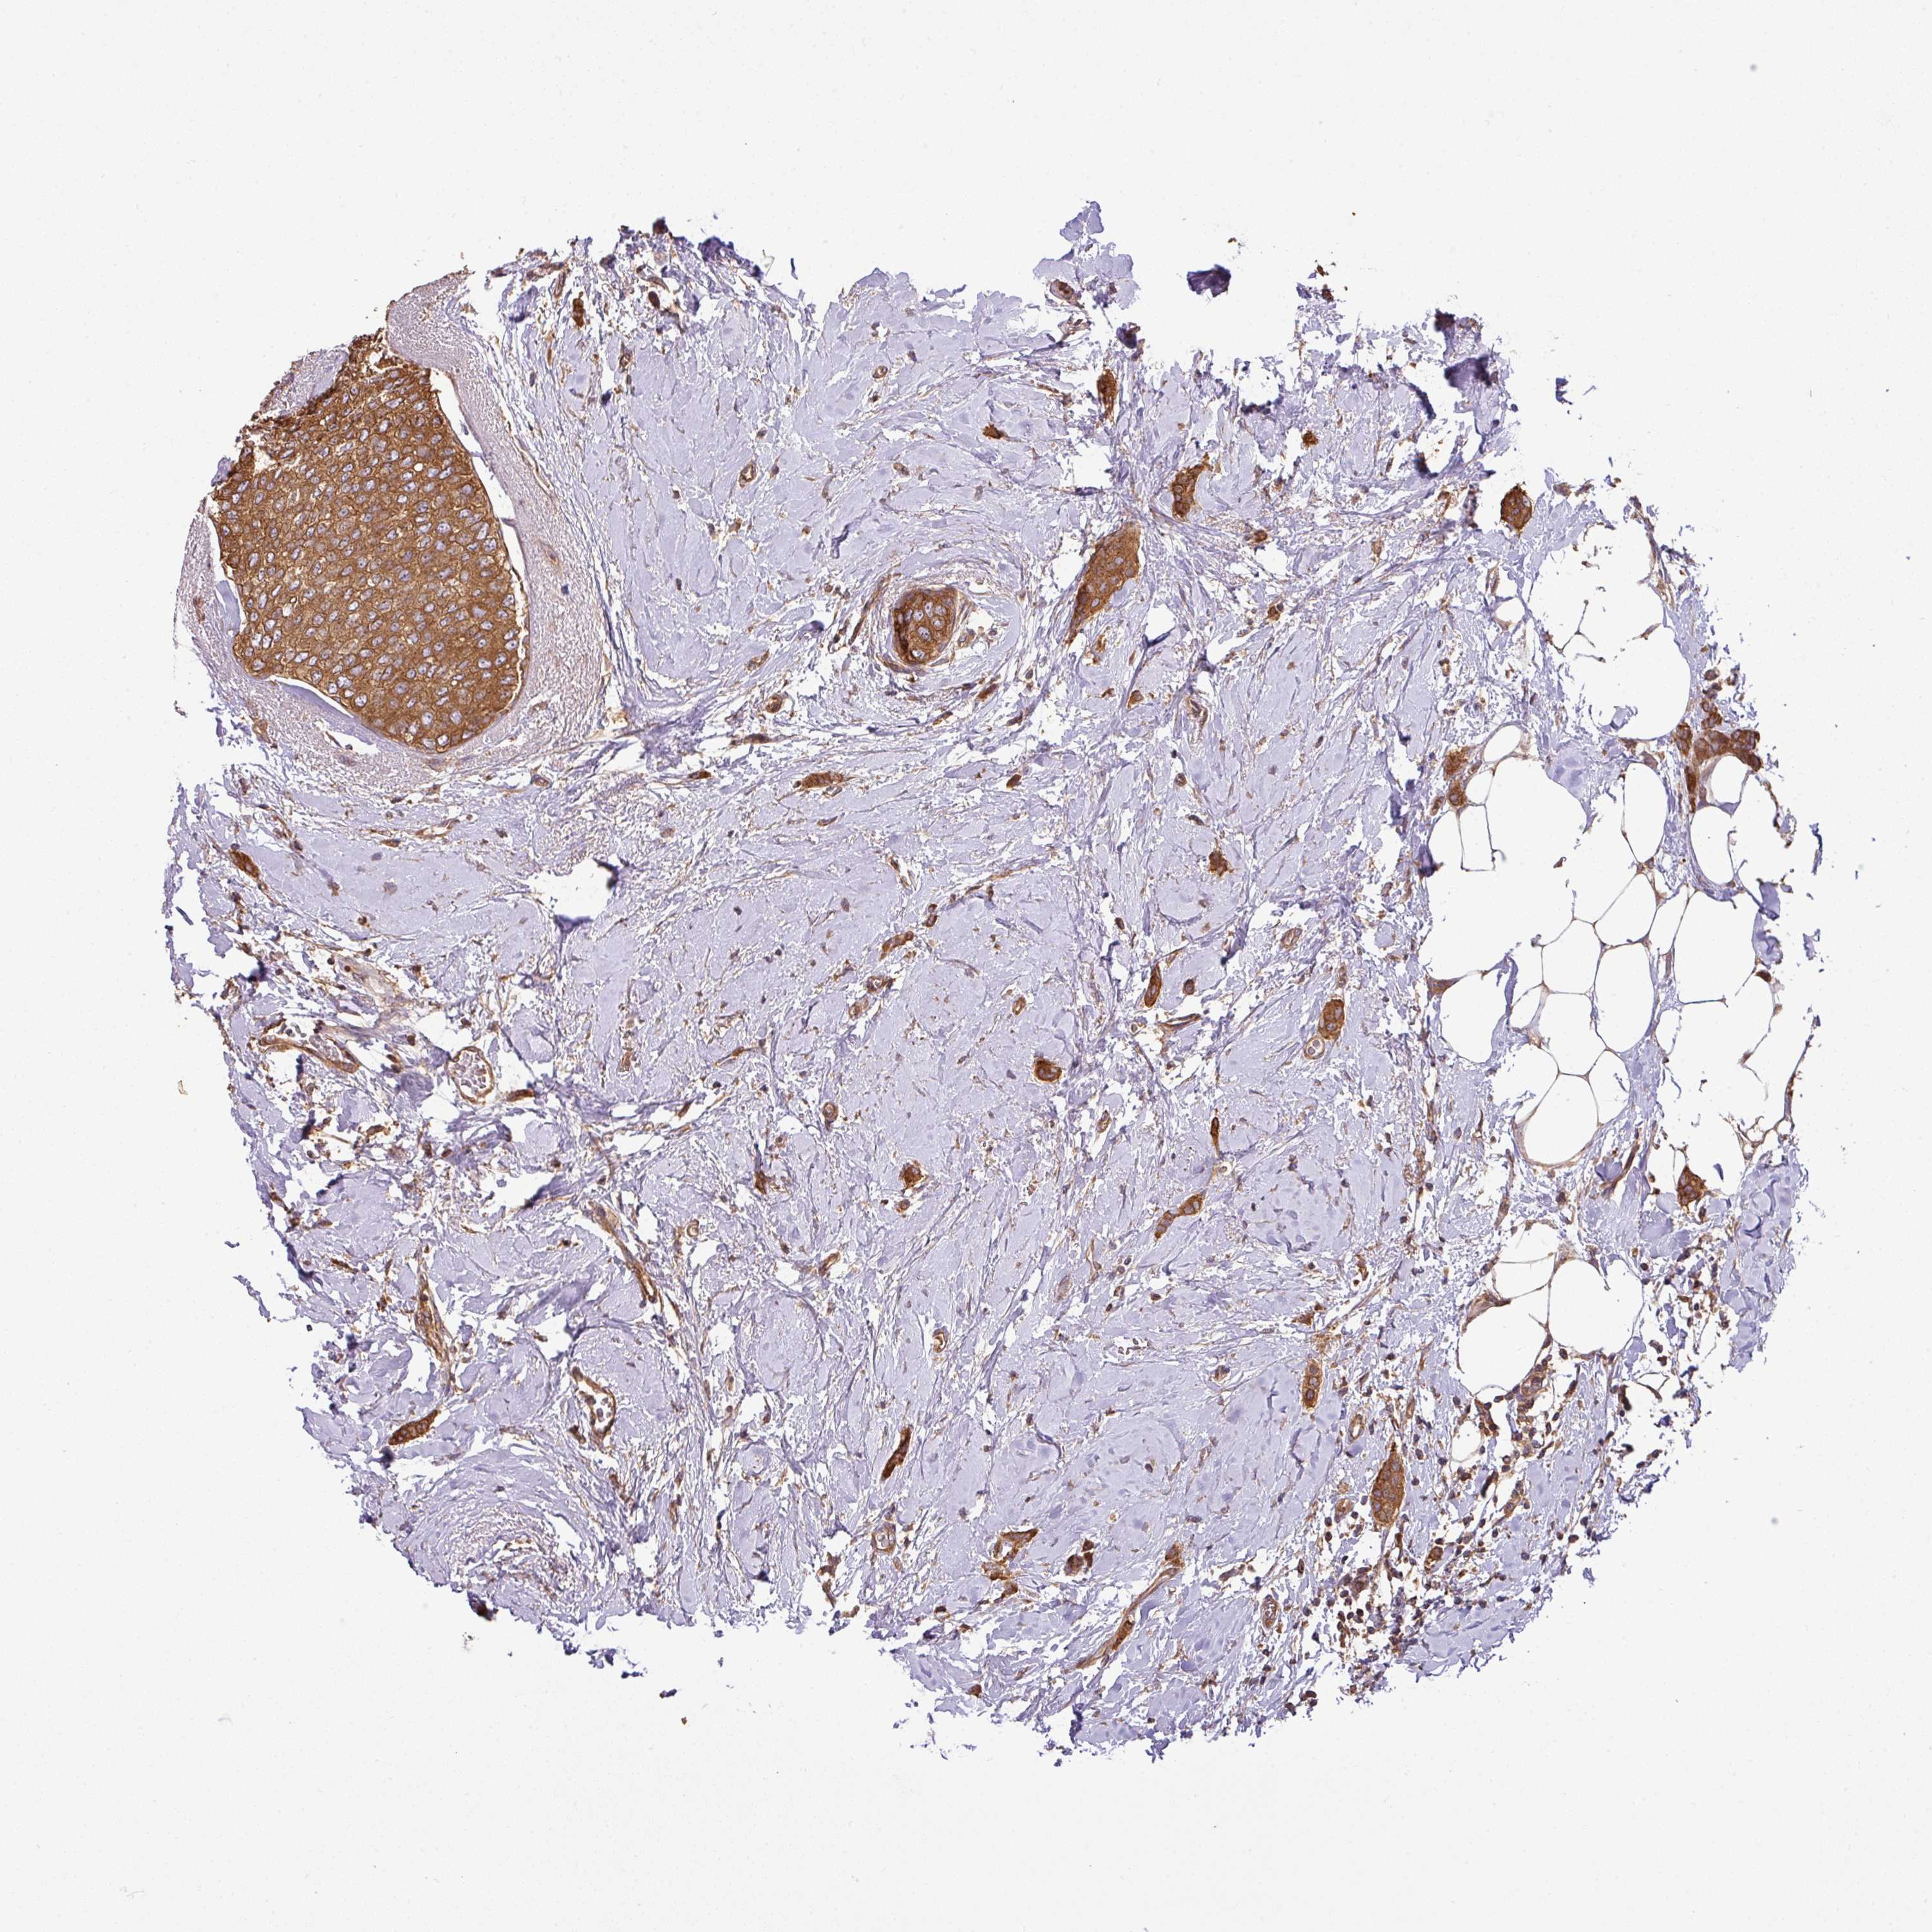

CANCER BREAST CANCER Show tissue menu

BRCA TCGA BRCA VALIDATION PROTEIN EXPRESSION

ANTIBODIES

AND

VALIDATION